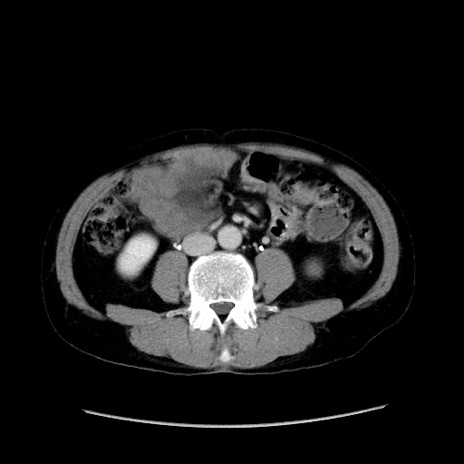

冠状断像

【症例】40歳代 男性

【主訴】腹痛

【現病歴】4時間ほど前に電車に乗車中に臍部上より腹痛出現。徐々に増悪し起立困難となり、救急外来受診。生ものは数日食べていない。今朝お雑煮を食べた。

【身体所見】BT 36.8℃、BP 117/84mmHg、HR 91/min、SpO2 97%、苦悶様、腹部:臍上部広範囲圧痛あり、反跳痛±

【データ】WBC 8100、CRP 0.03